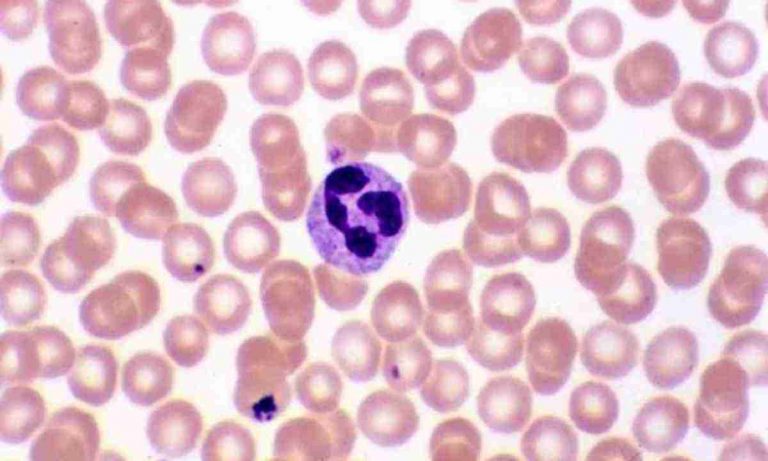

Кров пульсує тисячами невидимих вартових, серед яких нейтрофіли вирізняються як перша лінія оборони. Ці гранулоцити, що становлять...